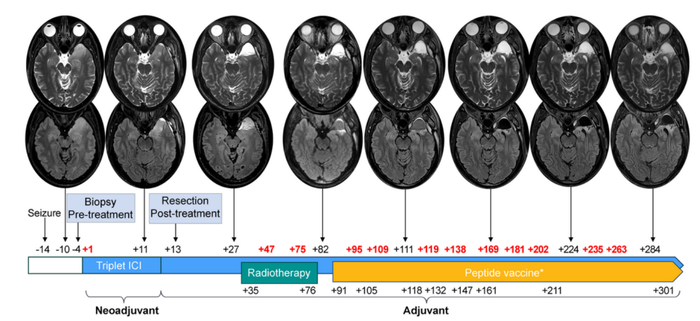

活检明确病理后,理查德先做了1个周期的三联免疫检查点阻断(ICI)治疗。12天后,完成GBM切除术。再接着,他做了局部放疗,又经历单药免疫治疗、纠正免疫不良反应后继续接受多联ICI,以及4次个体化肿瘤疫苗接种。

结果如他所料。理查德的肿瘤属WHO Ⅳ级、IDH野生型、MGMT未甲基化,几乎是GBM中预后最差的一类。但也有好消息:经过三联ICI后,组织内多处免疫细胞都有10倍以上增加,提示肿瘤微环境明显改变!

在2023年10月召开的欧洲肿瘤内科学会年会上,理查德的好友、同事兼诊疗团队负责人乔治娜·朗(Georgina Long)在主会场做专题发言,介绍理查德截至当时的治疗情况。

当地时间2024年5月14日,理查德通过社交媒体宣布,治疗近1年后,自己病情稳定、未检出GBM复发迹象。他表示,自己留取了宝贵的生物样本,包括新辅助治疗前后的脑肿瘤样本,整个治疗过程中的血、粪样本,以及脑脊液样本等,未来会进行更详细的转化研究。

其次,治疗反应评估是个难题。早期进行免疫治疗会导致炎症反应,或出现独特的影像学改变,看起来像是疾病在进展。实际上,一部分患者仍可以获得长期生存、肿瘤消退等临床获益。据此,RNAO协作组制定“免疫疗法RANO(iRANO)”来确定反应,防止接受免疫治疗的GBM患者过早地被判断为无反应者。